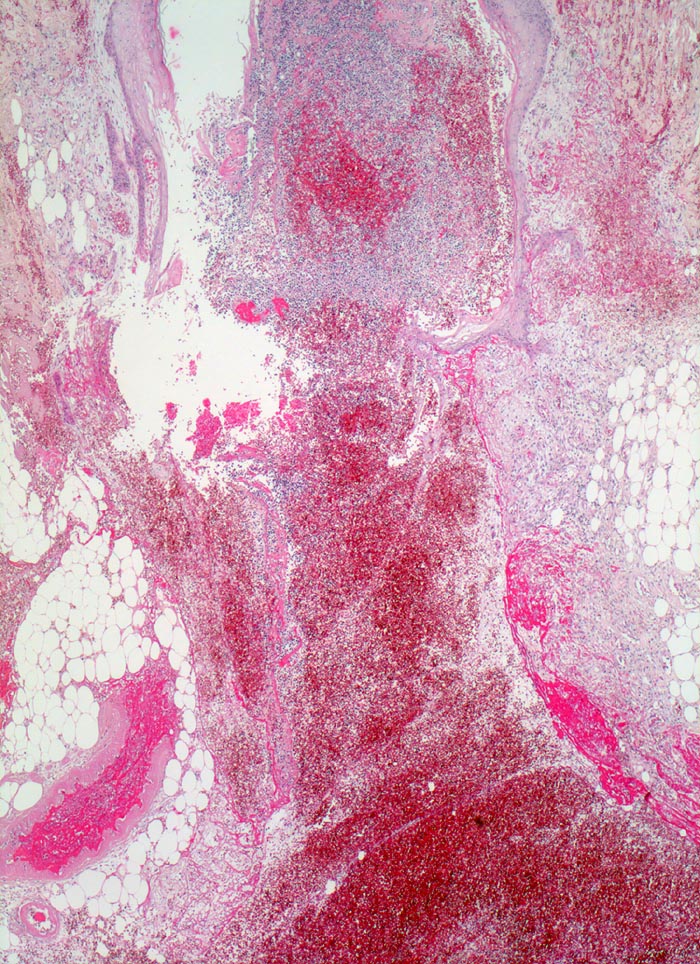

PathoPic ID 3572 - Wundheilung

Wundheilung

Entzündung / Reparatur

Haut, Rumpf

Haut

Spaltförmiger Defekt des Plattenepithels, der sich fortsetzt in die darunterliegende Cutis und obere Subcutis, mit spaltförmigem Defekt der Bindegewebsfasern. Am Rand des Defektes

Granulationsgewebsbildung und

Fibrinauflagerungen.

6 Tage alte Wunde am Abdomen nach Laparotomie.

Histologie

25